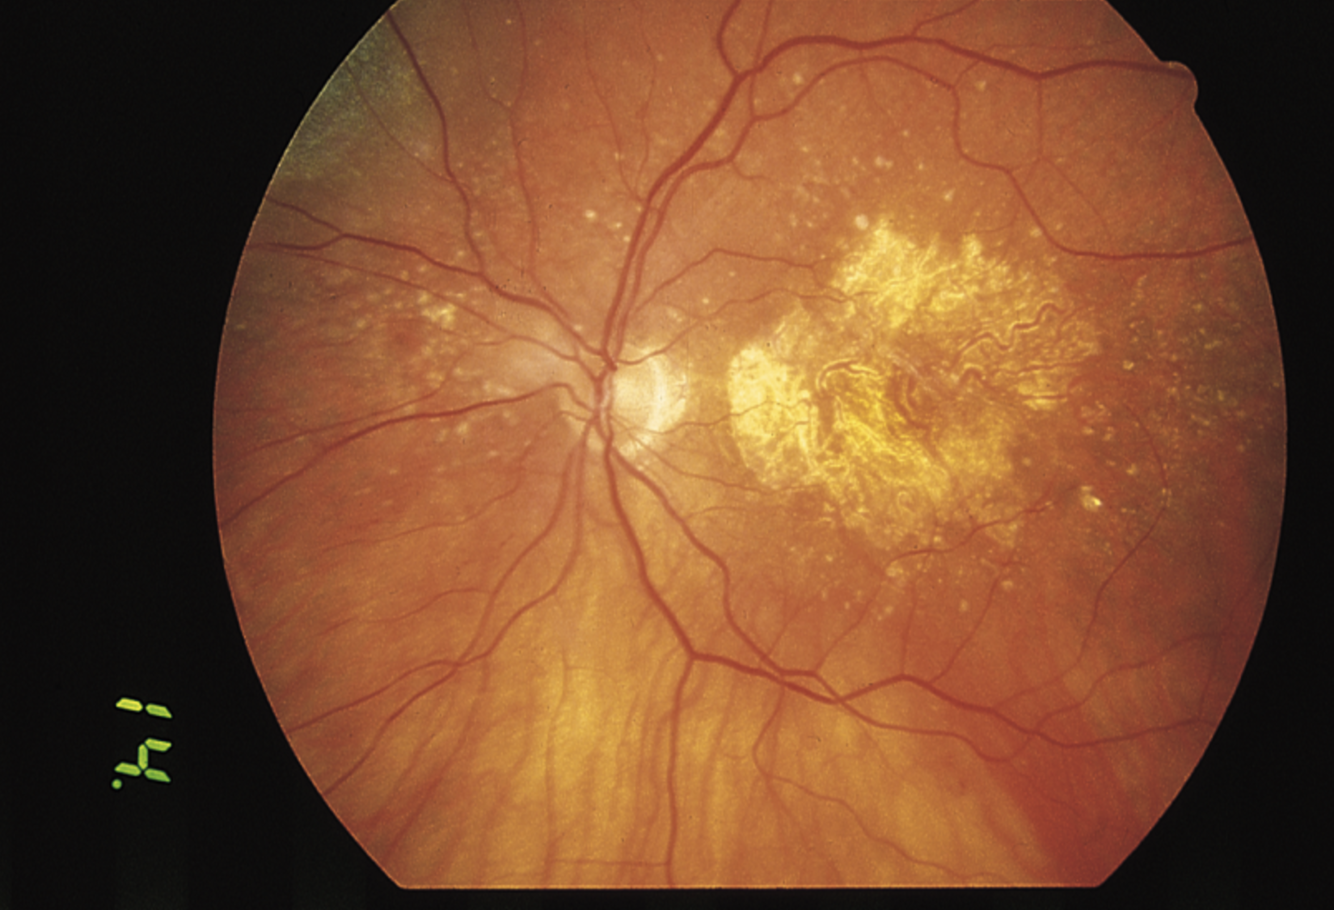

What form of macular degeneration

(donut looking structure = retinal pigment epithelium elevation, deep net of new vessels push it upward. also seen with hemorrage)

What is a typical sign of this condition?

The patient will say that tables look tilted and telephone poles look bent

(Wet Macular Degeneration - urgent)

Leaking sub retinal net in the fovea visualized via fluorescein angiography (injected into arm vein)

(trmt: anti-VEGF)